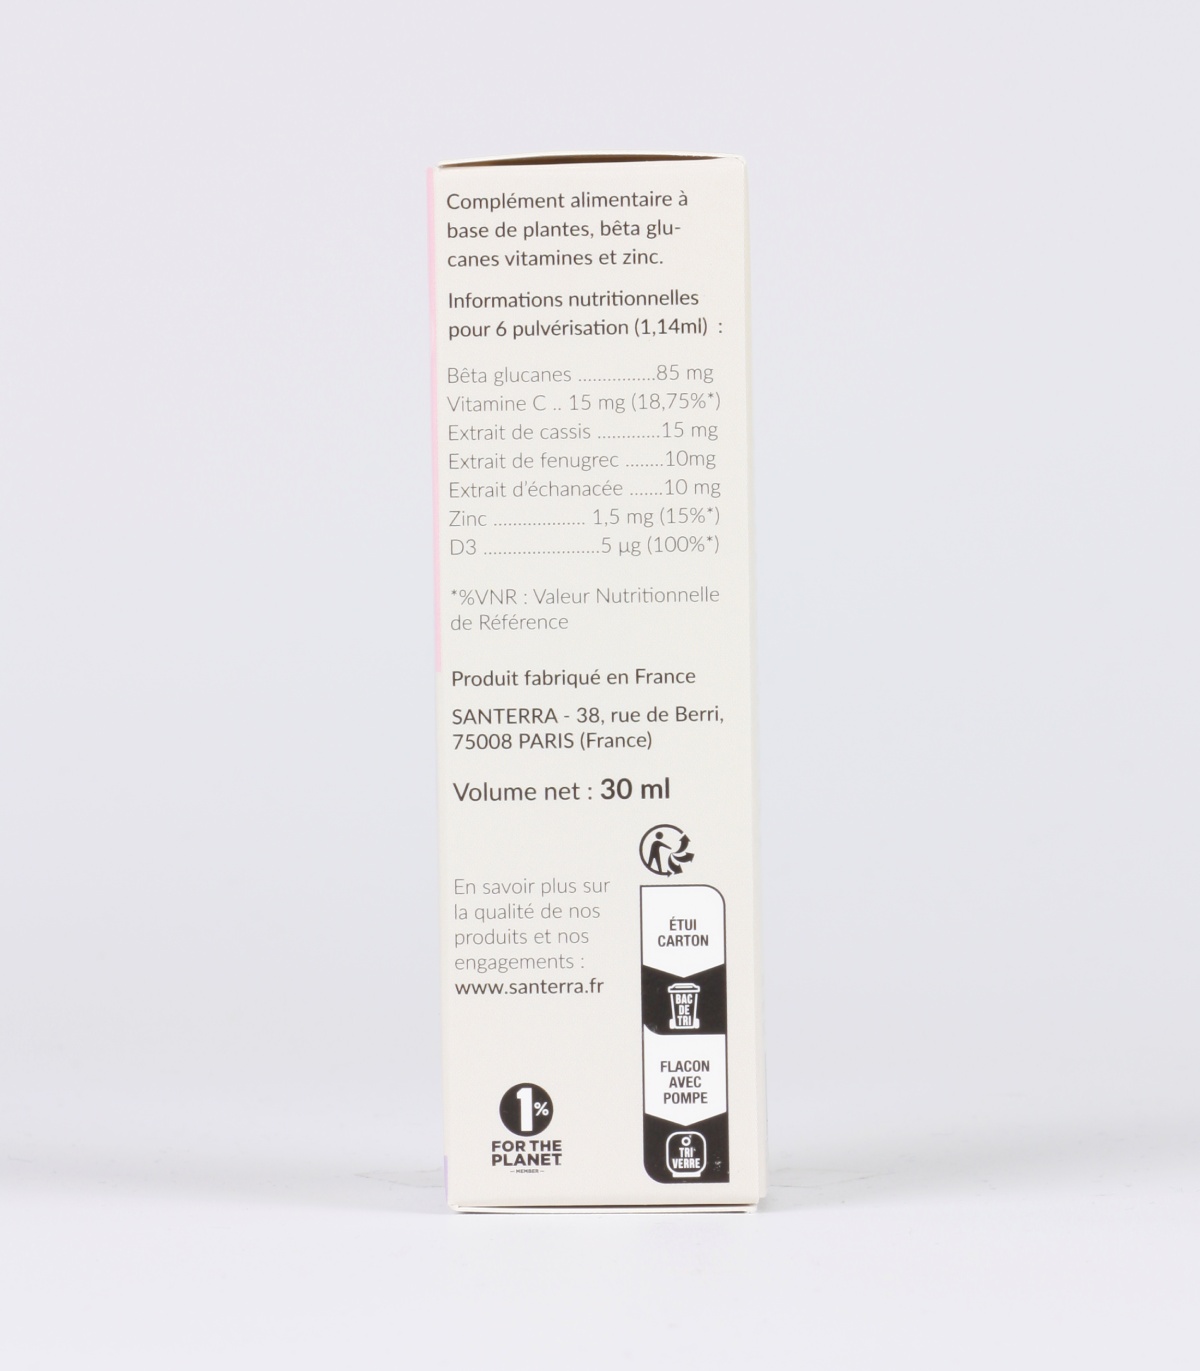

QUELLE EST LA COMPOSITION DE CALCIUM COMPLEXE SANTERRA?

Gélules composées de calcium avec cofacteurs

Sources de Calcium : Pidiolate de Calcium et bisglycinate de calcium TRAAC

Vitamine K2MK7 brevetée : MenaQ7® Matrix

Vitamine D3 naturelle issue de lichen Vitashine®

| Ingrédients | Dosage pour 2 gélules | Dosage pour 4 gélules |

|---|---|---|

| Bisglycinate de calcium | 577 mg | 1154 mg |

| – dont calcium | 150 mg (18,75%) | 300 mg (37,5%) |

| Pidolate de calcium | 389 mg | 778 mg |

| – dont calcium | 50 mg (6,25%) | 100 mg (12,5%) |

| Bisglycinate de magnésium | 166 mg | 333 mg |

| – dont magnésium | 30 mg (8%) | 60 mg (16%) |

| Vitamine K2 (MK7) | 80 μg (106,5%) | 160 μg (213%) |

| Vitamine D3 | 0.5 μg (10%) | 1 μg (20%) |

Ingrédients : Bisglycinate de calcium, pidolate de calcium, tunique : gélifiant hydroxypropylméthylcellulose, bisglycinate de magnésium, ménaquinone-7 (vitamine K2-MK7), antiagglomérant : acide stéarique, cholécalciférol végétal (vitamine D3).